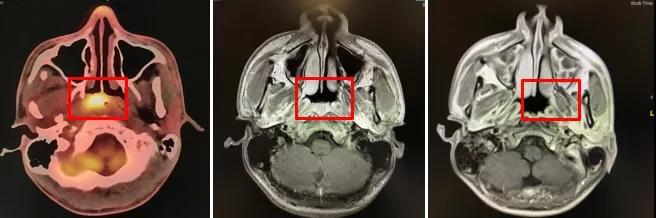

PET-CT(2020年2月17日):鼻咽顶后壁、右侧壁黏膜增厚,范围约31mm×31mm×32mm,SUV 12.7,符合鼻咽癌表现;右侧颈部II-V区多发转移淋巴结,大者直径约40mm,如图1-1所示;右侧髂骨髂后上棘SUV 14.5,考虑骨转移,如图1-2所示。